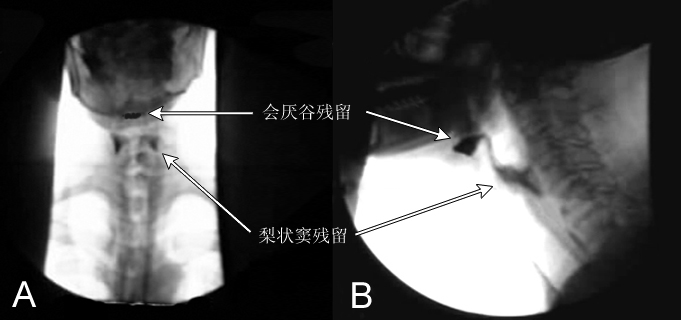

在此情况下,我院为患者进行了吞咽功能障碍X线钡餐造影检查。这项技术通过特殊的造影剂,清晰展示出患者的整个吞咽过程,从而精准识别出吞咽障碍的具体表现和原因。这不仅有助于我们了解患者的病情,更为后续的临床治疗方案提供了科学、准确的依据。

独特优势:自口咽至食管上段的过程十分迅速,只有X线动态造影录像或快速摄片才能记录其活动,并且可以逐步慢速回放。此外,吞咽造影检查还可以用于协助诊治吞咽障碍,被视为吞咽障碍的“理想”方法和诊断的“金标准”。通过食团的传送,在正位、侧位动态观察咽部运动,为治疗吞咽功能障碍提供了有效依据。